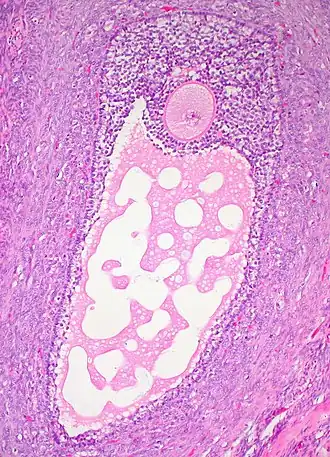

![]() Histology section of a mature ovarian follicle. The oocyte is the large, round, pink-staining cell at top center of the image. | |

An ovarian follicle is a roughly spheroid cellular aggregation set found in the ovaries. It secretes hormones that influence stages of the menstrual cycle. In humans, women have approximately 200,000 to 300,000 follicles at the time of puberty,[1][2] each with the potential to release an egg cell (ovum) at ovulation for fertilization.[3] These eggs are developed once every menstrual cycle with around 300-400 being ovulated during a woman's reproductive lifetime.[4]

Ovarian follicles are the basic units of female reproductive biology. Each of them contains a single oocyte (immature ovum or egg cell). These structures are periodically initiated to grow and develop, culminating in ovulation of usually a single competent oocyte in humans.[5] They also consist of granulosa cells and theca of follicle.